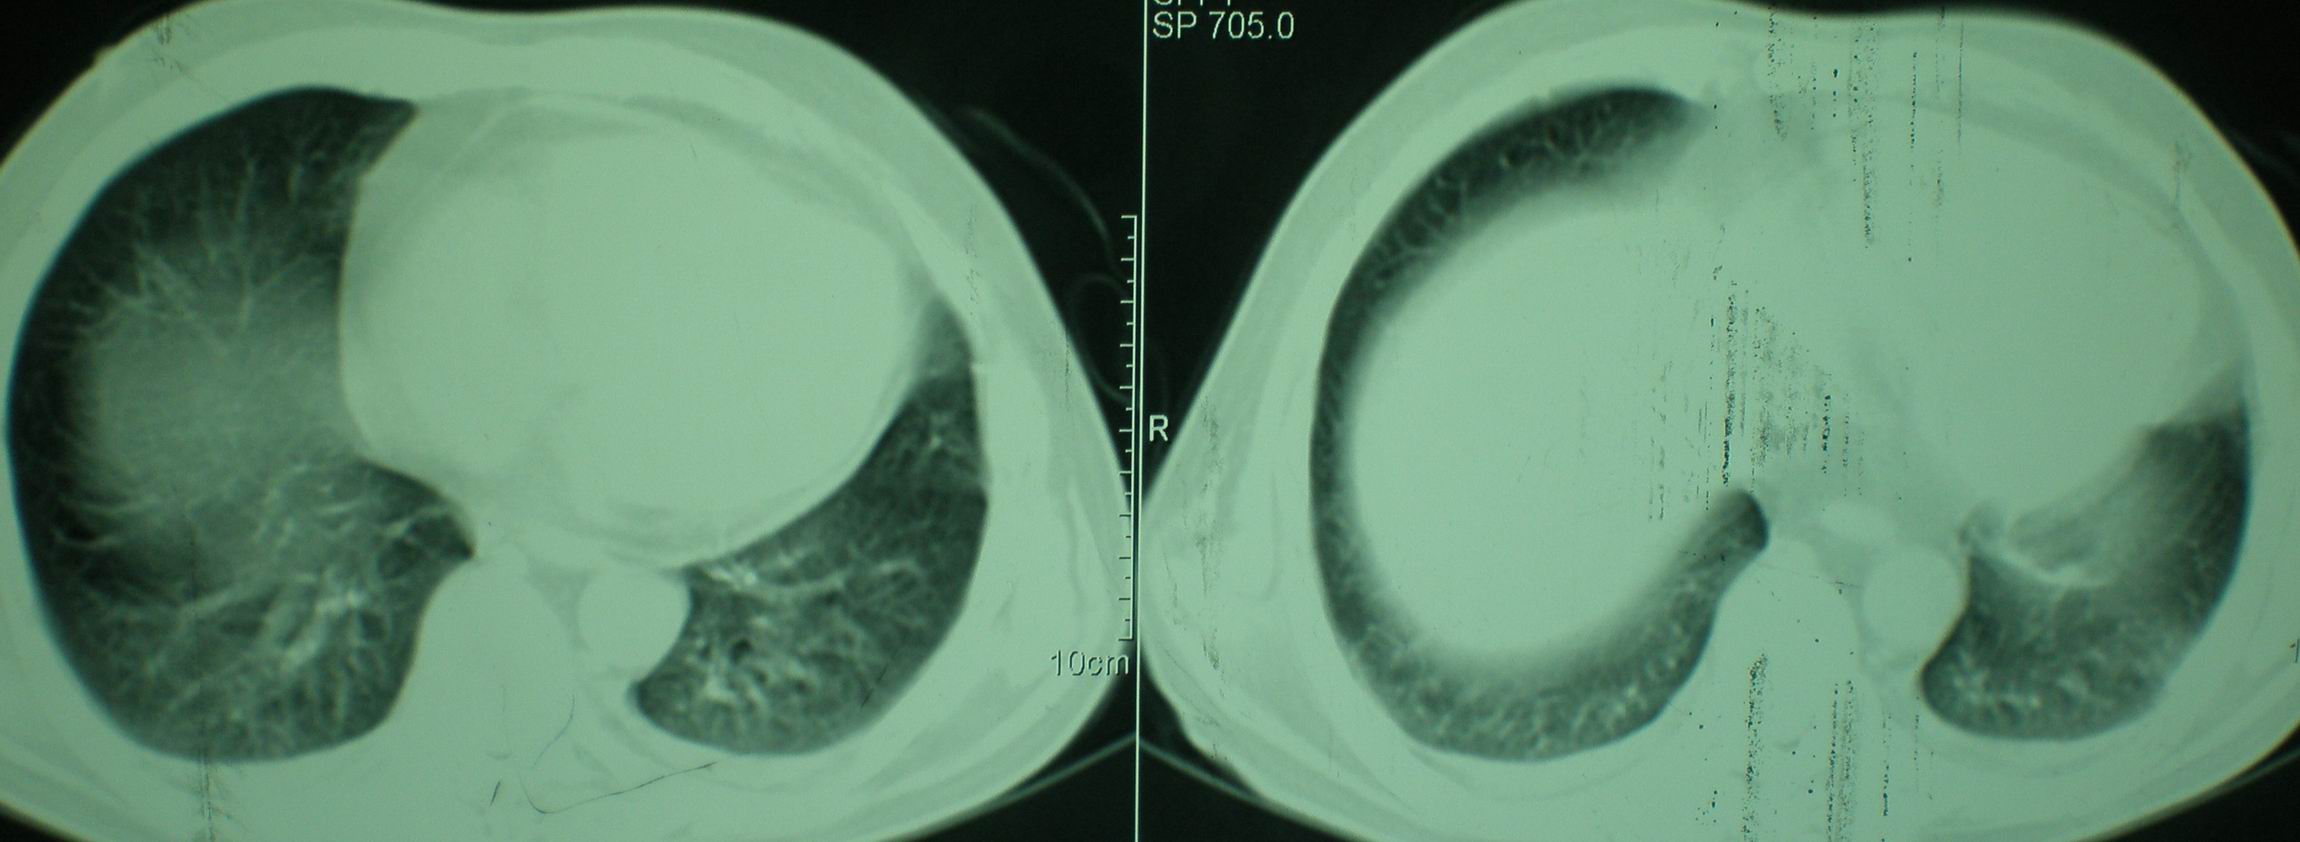

2008年9月8日ct片:

[face=宋体]显然上级医院进行了抗结核,抗真菌,抗炎等治疗,目前病人肺内病灶基本消失,双侧胸腔积液,右侧积液量有吸收,抗结核一个多月,现在病人疑问,结核的诊断是否有疑义,抗结核是否继续,因为那个毕竟副作用大。[/face]

急性心衰所致肺水肿,双侧胸腔积液,少量心包积液可能?结合临床及其它检查.

我仔细看了下病人的出院小结,当时情况危急,诊断里有1型呼衰。心包周围的是脂肪密度。结合三次ct扫描的图象分析,个人认为:1、病人目前肺部病灶基本消失,双侧胸腔内少量积液,抗结核治疗才一个多月,就算是结核,抗结核治疗有效果,为何效果如此好,一点纤维灶的痕迹都没有呢,再就是患者做过气管镜检查及活检、痰检均未找到结核的证据。所以不支持结核的诊断。

2、结合现在的ct片,考虑:肺水肿及真菌感染,双侧胸腔积液。

急性呼吸窘迫综合征,肺水肿,与激素减量太快有关.双侧胸腔积液.